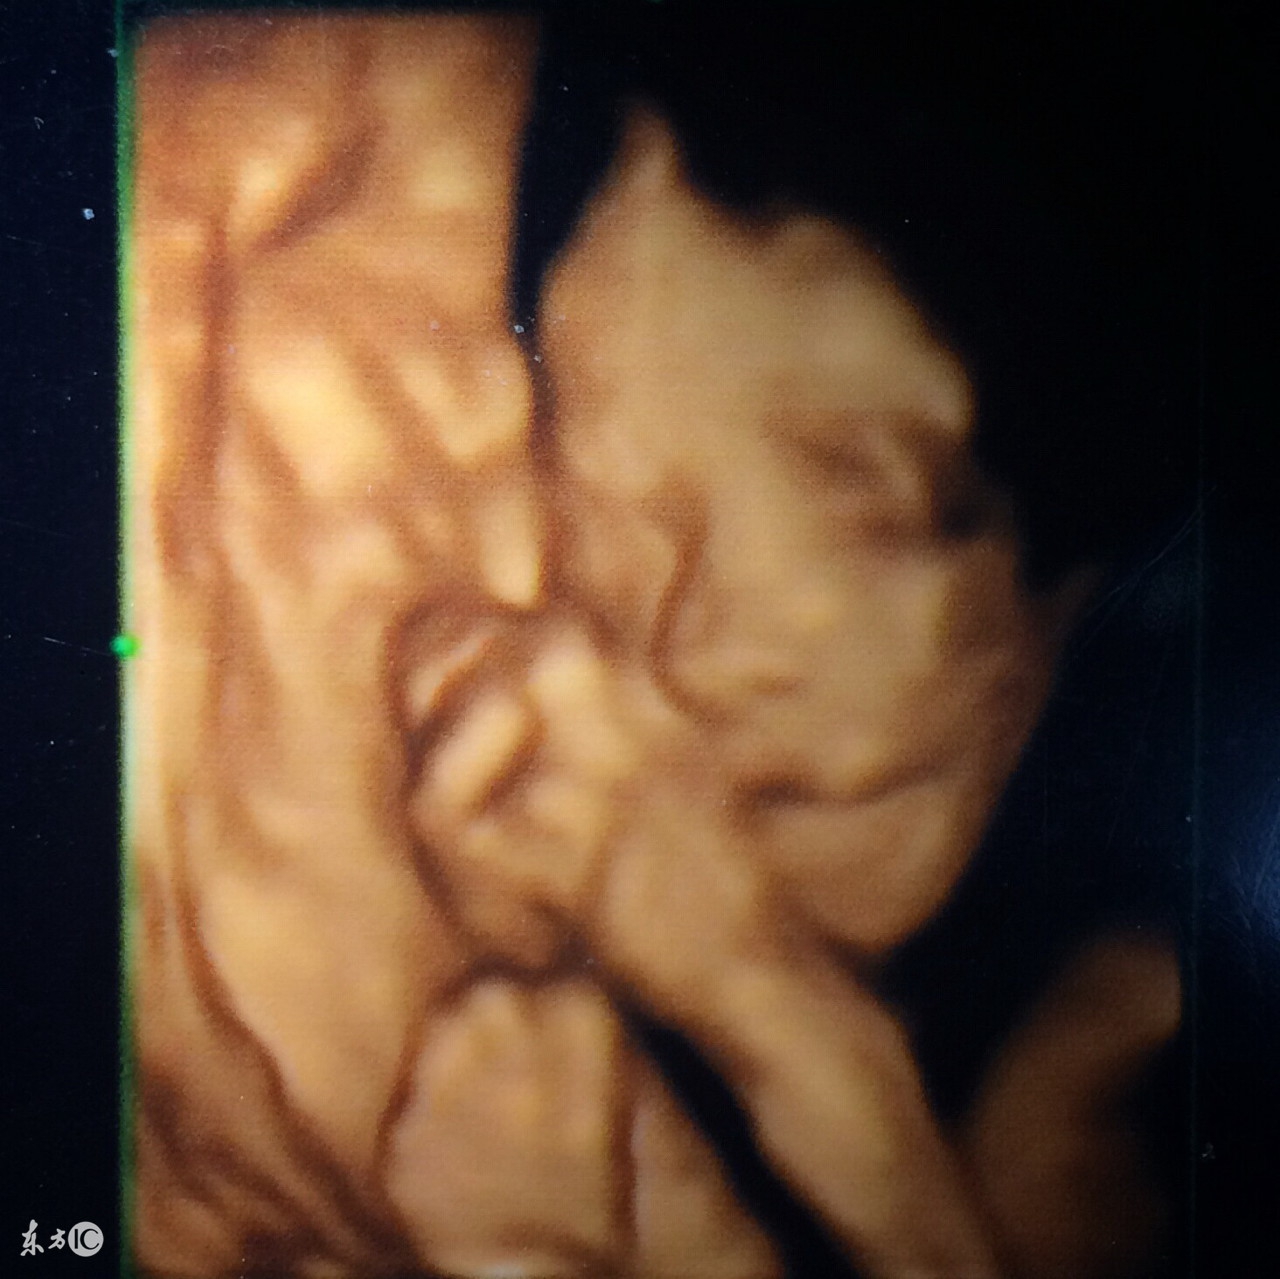

6、四维彩超:可能是土黄色,录像,动态,能够刻录成光盘,有排畸作用;

四维彩超也称大排畸检查,做四维彩超的最佳时间是在24-28周,这时宫内空间大,宝宝活动方便,回声比较小,图像会更加清楚。